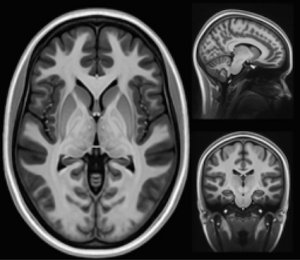

La maladie de Charcot, ou sclérose latérale amyotrophique (SLA), est une pathologie neurodégénérative qui détruit progressivement les neurones moteurs. Ce sont eux qui commandent les muscles. Quand ils meurent, le corps cesse d’obéir. Les muscles s’atrophient, la parole devient difficile, la déglutition se complique, puis la respiration elle-même finit par être atteinte. Le cerveau, lui, reste souvent intact. C’est ça qui rend la maladie particulièrement violente : lucidité totale dans un corps qui lâche.

D’abord, parce qu’on diagnostique mieux. Avant, beaucoup de patients étaient classés dans d’autres maladies neurologiques. Aujourd’hui, avec l’imagerie, les critères médicaux plus précis et la vigilance accrue, on identifie davantage de cas. Donc mécaniquement, les chiffres montent.